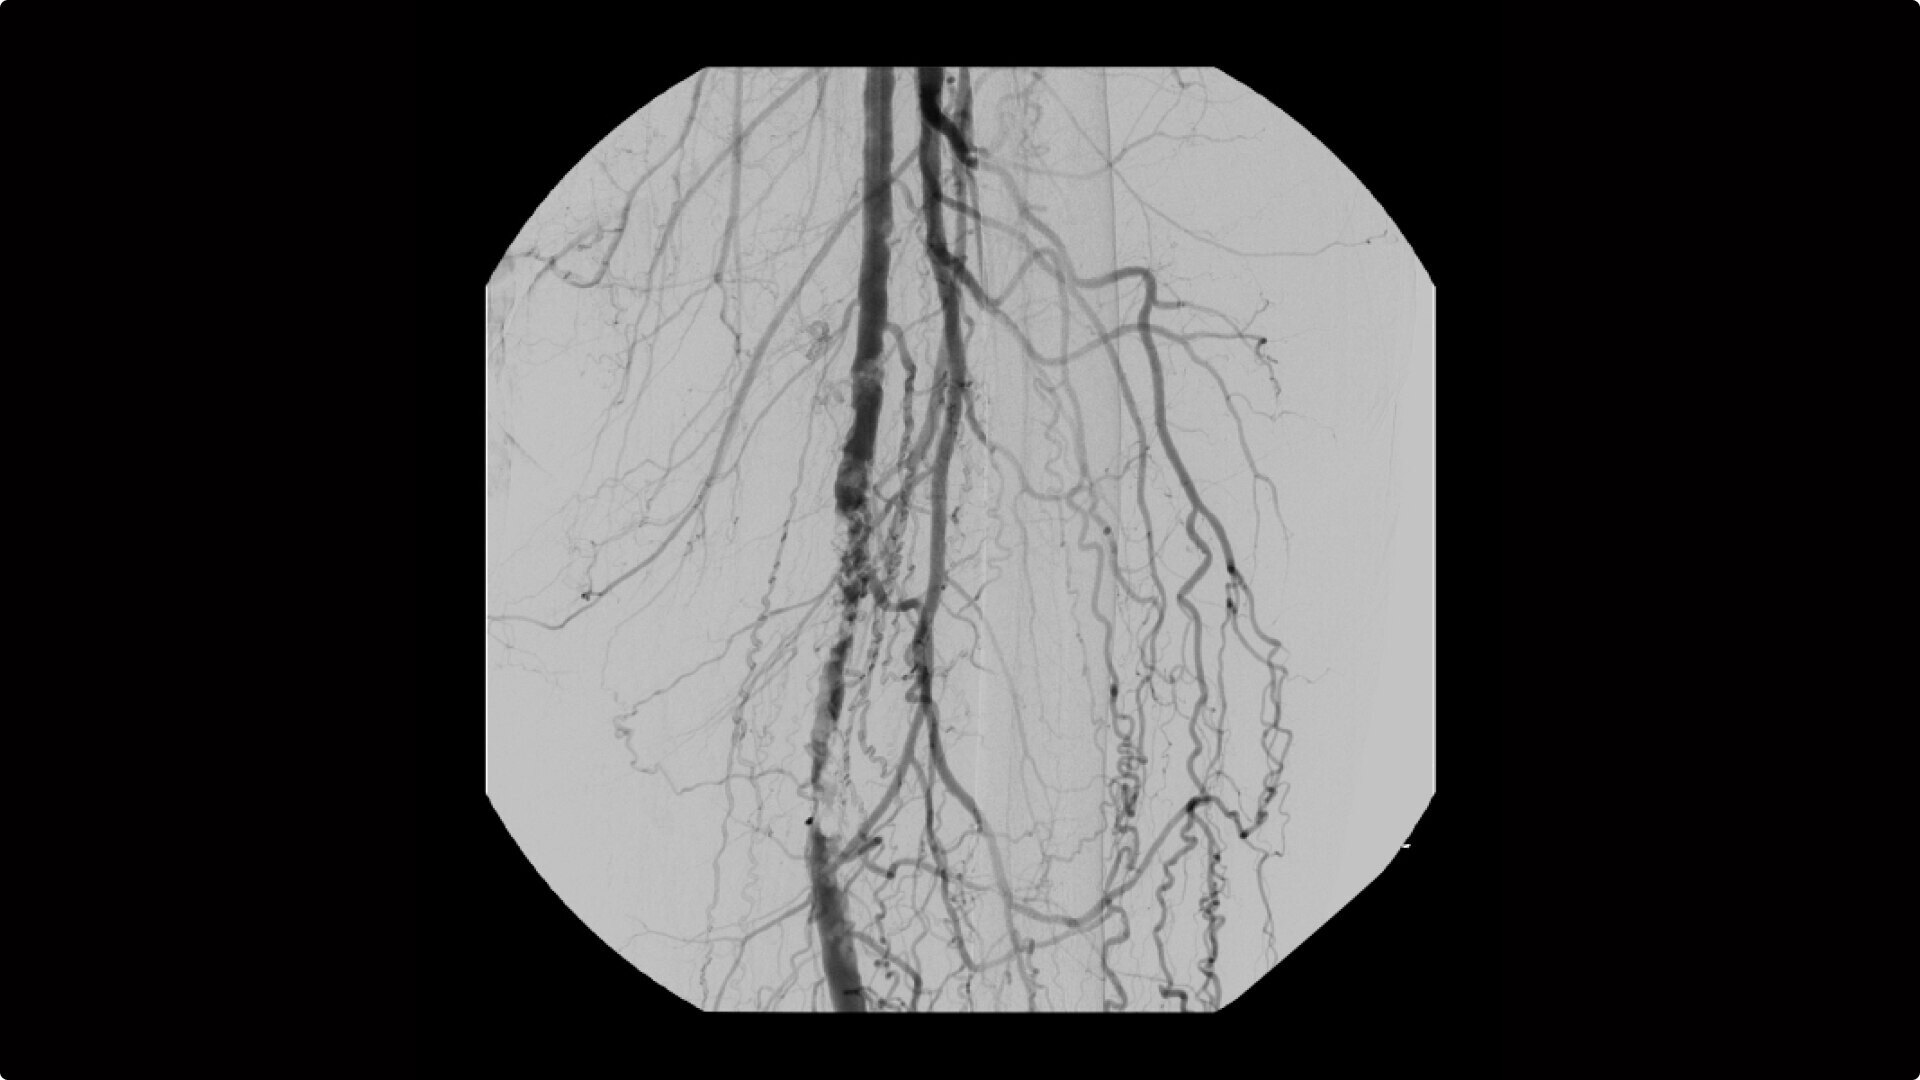

Clearly see 0.014” guidewires in chest and abdomen region or 0.008” guidewires in peripheral vascular with the OEC Elite CFD with a flat detector, image processing advancements and 4K viewing display.

Experience fixed room-like images with eNR (enhanced Noise Reduction), an advanced software algorithm that automatically reduces image noise by 30% for an equivalent appearance of 30 kW power.